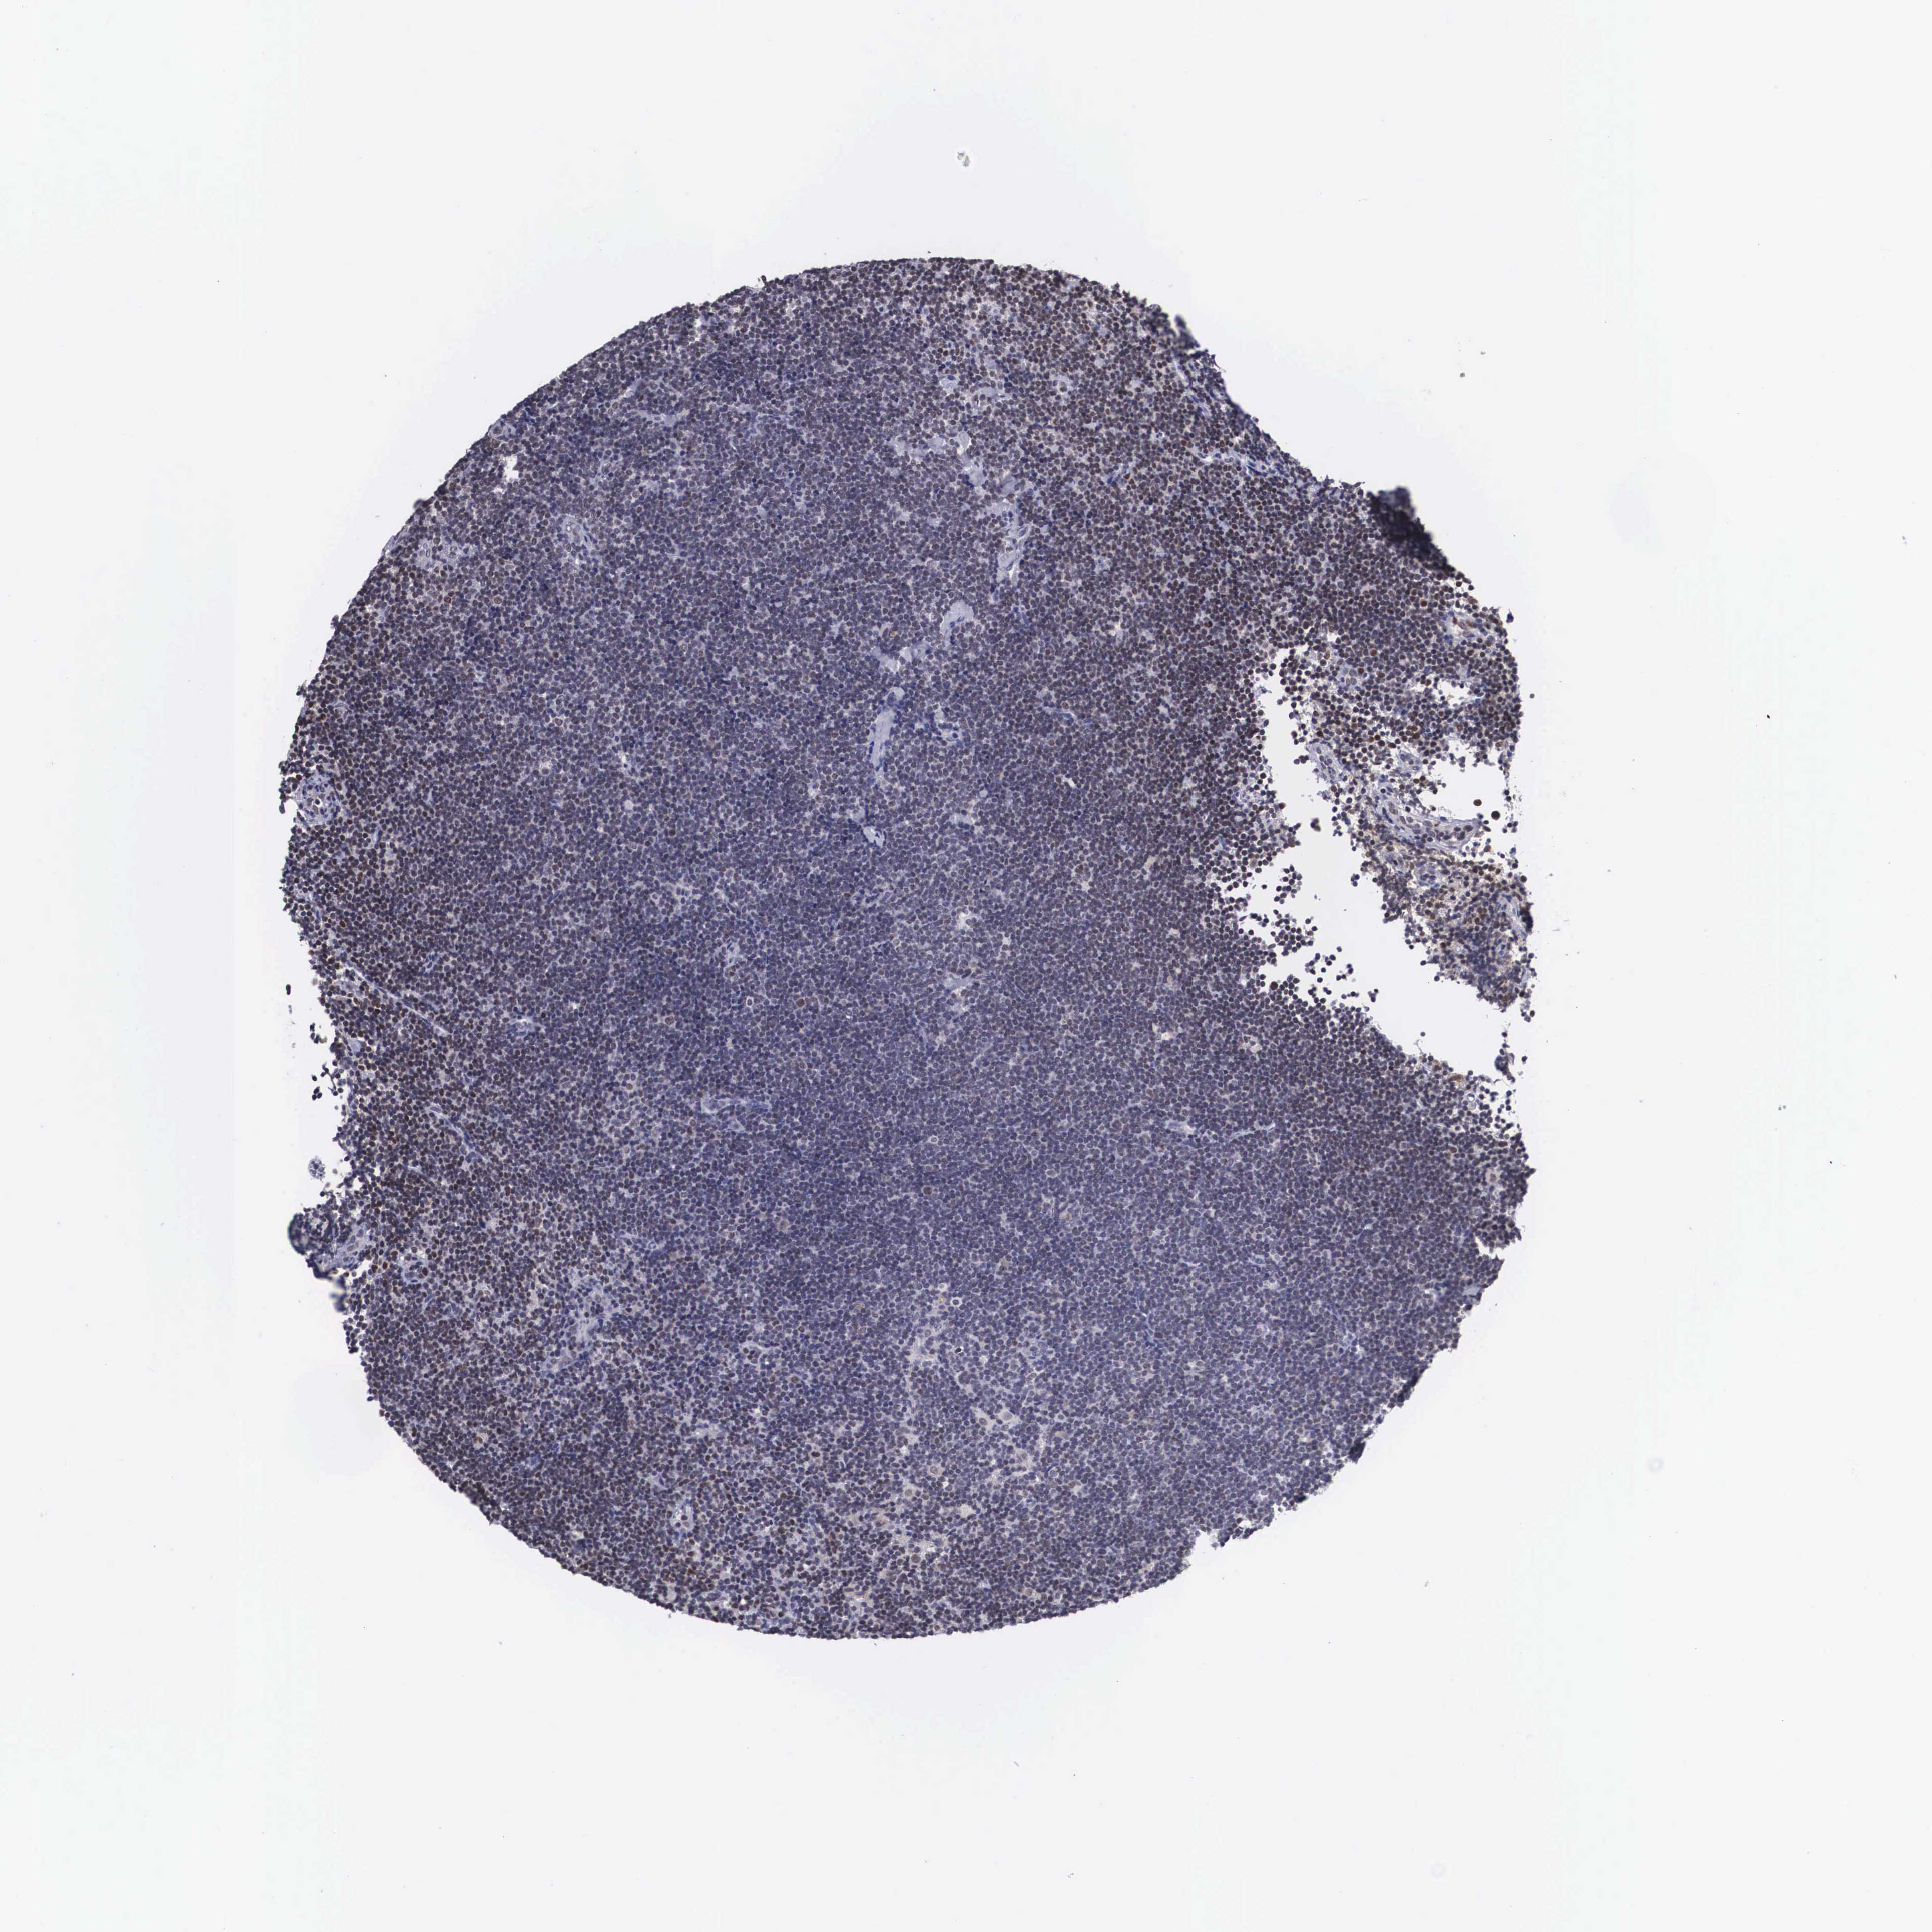

CANCER LYMPHOMA Show tissue menu

LYMPHOMA - Protein expressioni

A mouse-over function shows sample information and annotation data. Click on an image to view it in a full screen mode. Samples can be filtered based on level of antibody staining by selecting one or several of the following categories: high, medium, low and not detected. The assay and annotation is described here.

Each image is clickable and will lead to virtual microscopy that enables deeper exploration of all samples and also displays staining intensity scores, fraction scores and subcellular localization as well as patient and tissue information for each sample.

Antibody HPA000566

Staining

High

Intensity

Strong

Quantity

>75%

Location

Nuclear

Malignant lymphoma, non-Hodgkin's type, High grade

Malignant lymphoma, non-Hodgkin's type, Low grade